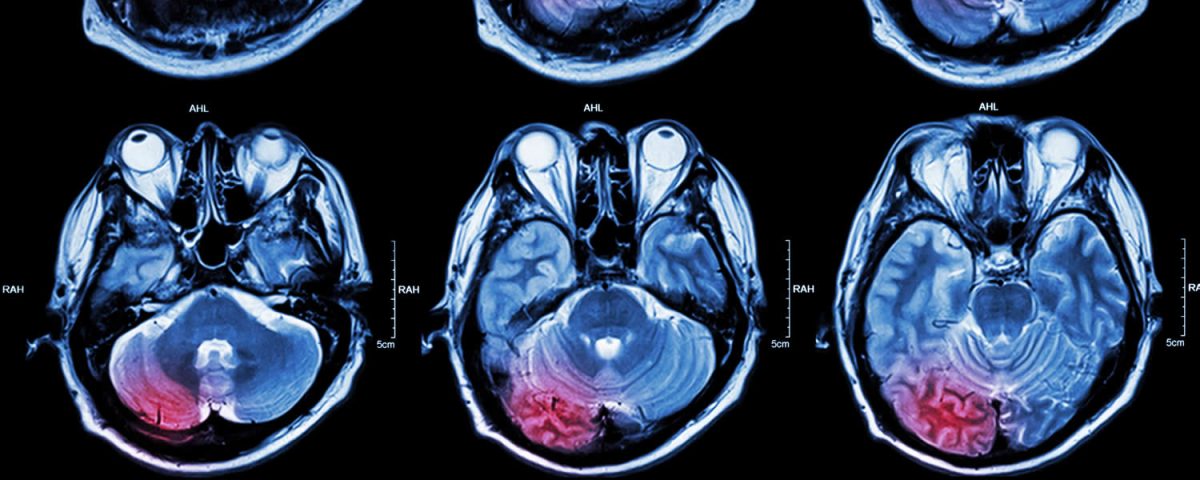

O AVC é um problema grave de saúde, e ocorre quando uma artéria do cérebro é obstruída por um coágulo ou rompe em algum ponto, provocando o extravasamento do sangue (hemorragia). Desta maneira, o AVC é conhecido no meio médico como AVC i, de isquêmico ou AVC h, de hemorrágico.

A prevenção do AVC se faz através da mudança de hábitos. A principal causa do AVC é a hipertensão arterial. As altas pressões dentro dos vasos promovem um enrijecimento dos mesmos, facilitando a progressão das placas de gordura no corpo inteiro, inclusive nos vasos do cérebro. Outra causa cardiológica comum de AVC é a fibrilação atrial, arritmia que gera trombos no coração e assim eles se deslocam, podendo se alojar nos pulmões (tromboembolismo pulmonar) ou no cérebro, ocasionando o AVC isquêmico.

Os principais sintomas do AVC é a perda de alguma função do corpo, seja cognitiva (deixar de falar) ou motora (desvio do lábio, perda de força súbita em algum lado do corpo). Ao presenciar alguém manifestando estes sintomas, a pessoa deve ligar imediatamente para o SAMU (192), e fazer um chamado de urgência. Quanto mais cedo a artéria for desobstruída, menor as sequelas. Tempo é cérebro!